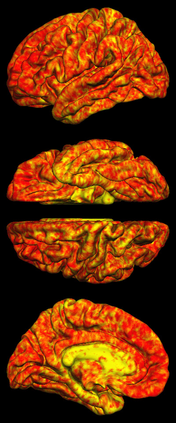

Due to various physical degradation factors and limited counts received, PET image quality needs further improvements. The denoising diffusion probabilistic models (DDPM) are distribution learning-based models, which try to transform a normal distribution into a specific data distribution based on iterative refinements. In this work, we proposed and evaluated different DDPM-based methods for PET image denoising. Under the DDPM framework, one way to perform PET image denoising is to provide the PET image and/or the prior image as the network input. Another way is to supply the prior image as the input with the PET image included in the refinement steps, which can fit for scenarios of different noise levels. 120 18F-FDG datasets and 140 18F-MK-6240 datasets were utilized to evaluate the proposed DDPM-based methods. Quantification show that the DDPM-based frameworks with PET information included can generate better results than the nonlocal mean and Unet-based denoising methods. Adding additional MR prior in the model can help achieve better performance and further reduce the uncertainty during image denoising. Solely relying on MR prior while ignoring the PET information can result in large bias. Regional and surface quantification shows that employing MR prior as the network input while embedding PET image as a data-consistency constraint during inference can achieve the best performance. In summary, DDPM-based PET image denoising is a flexible framework, which can efficiently utilize prior information and achieve better performance than the nonlocal mean and Unet-based denoising methods.